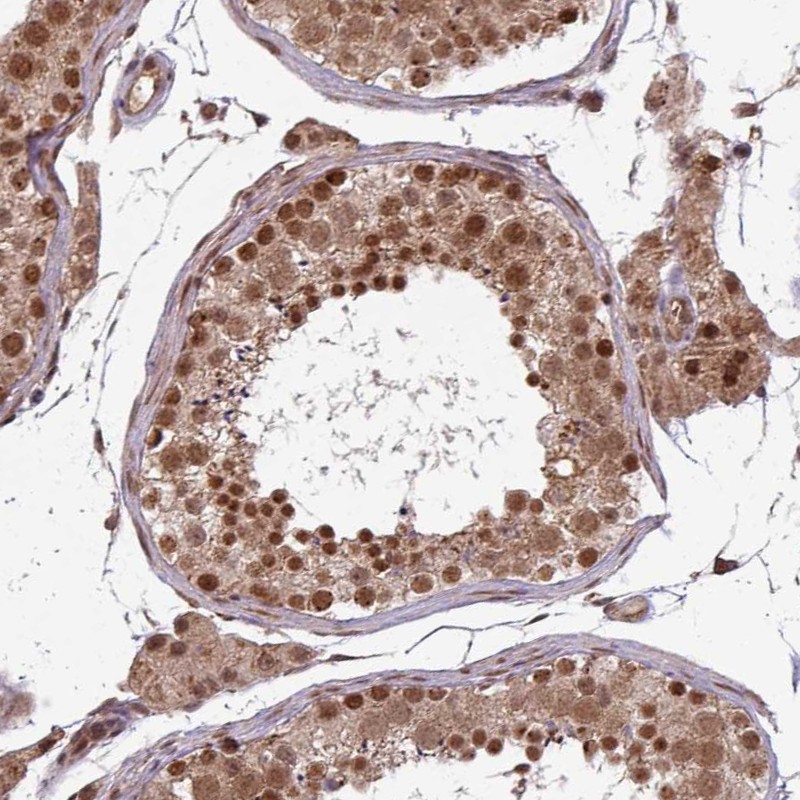

Immunohistochemical staining of human testis shows nuclear and cytoplasmic positivity in cells in seminiferous ducts and in Leydig cells.